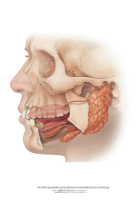

Suutervis

koolis

Kiku